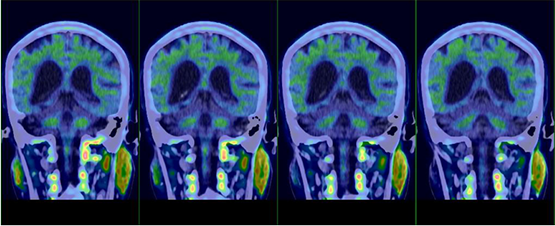

術前PET-CT檢查明確診斷